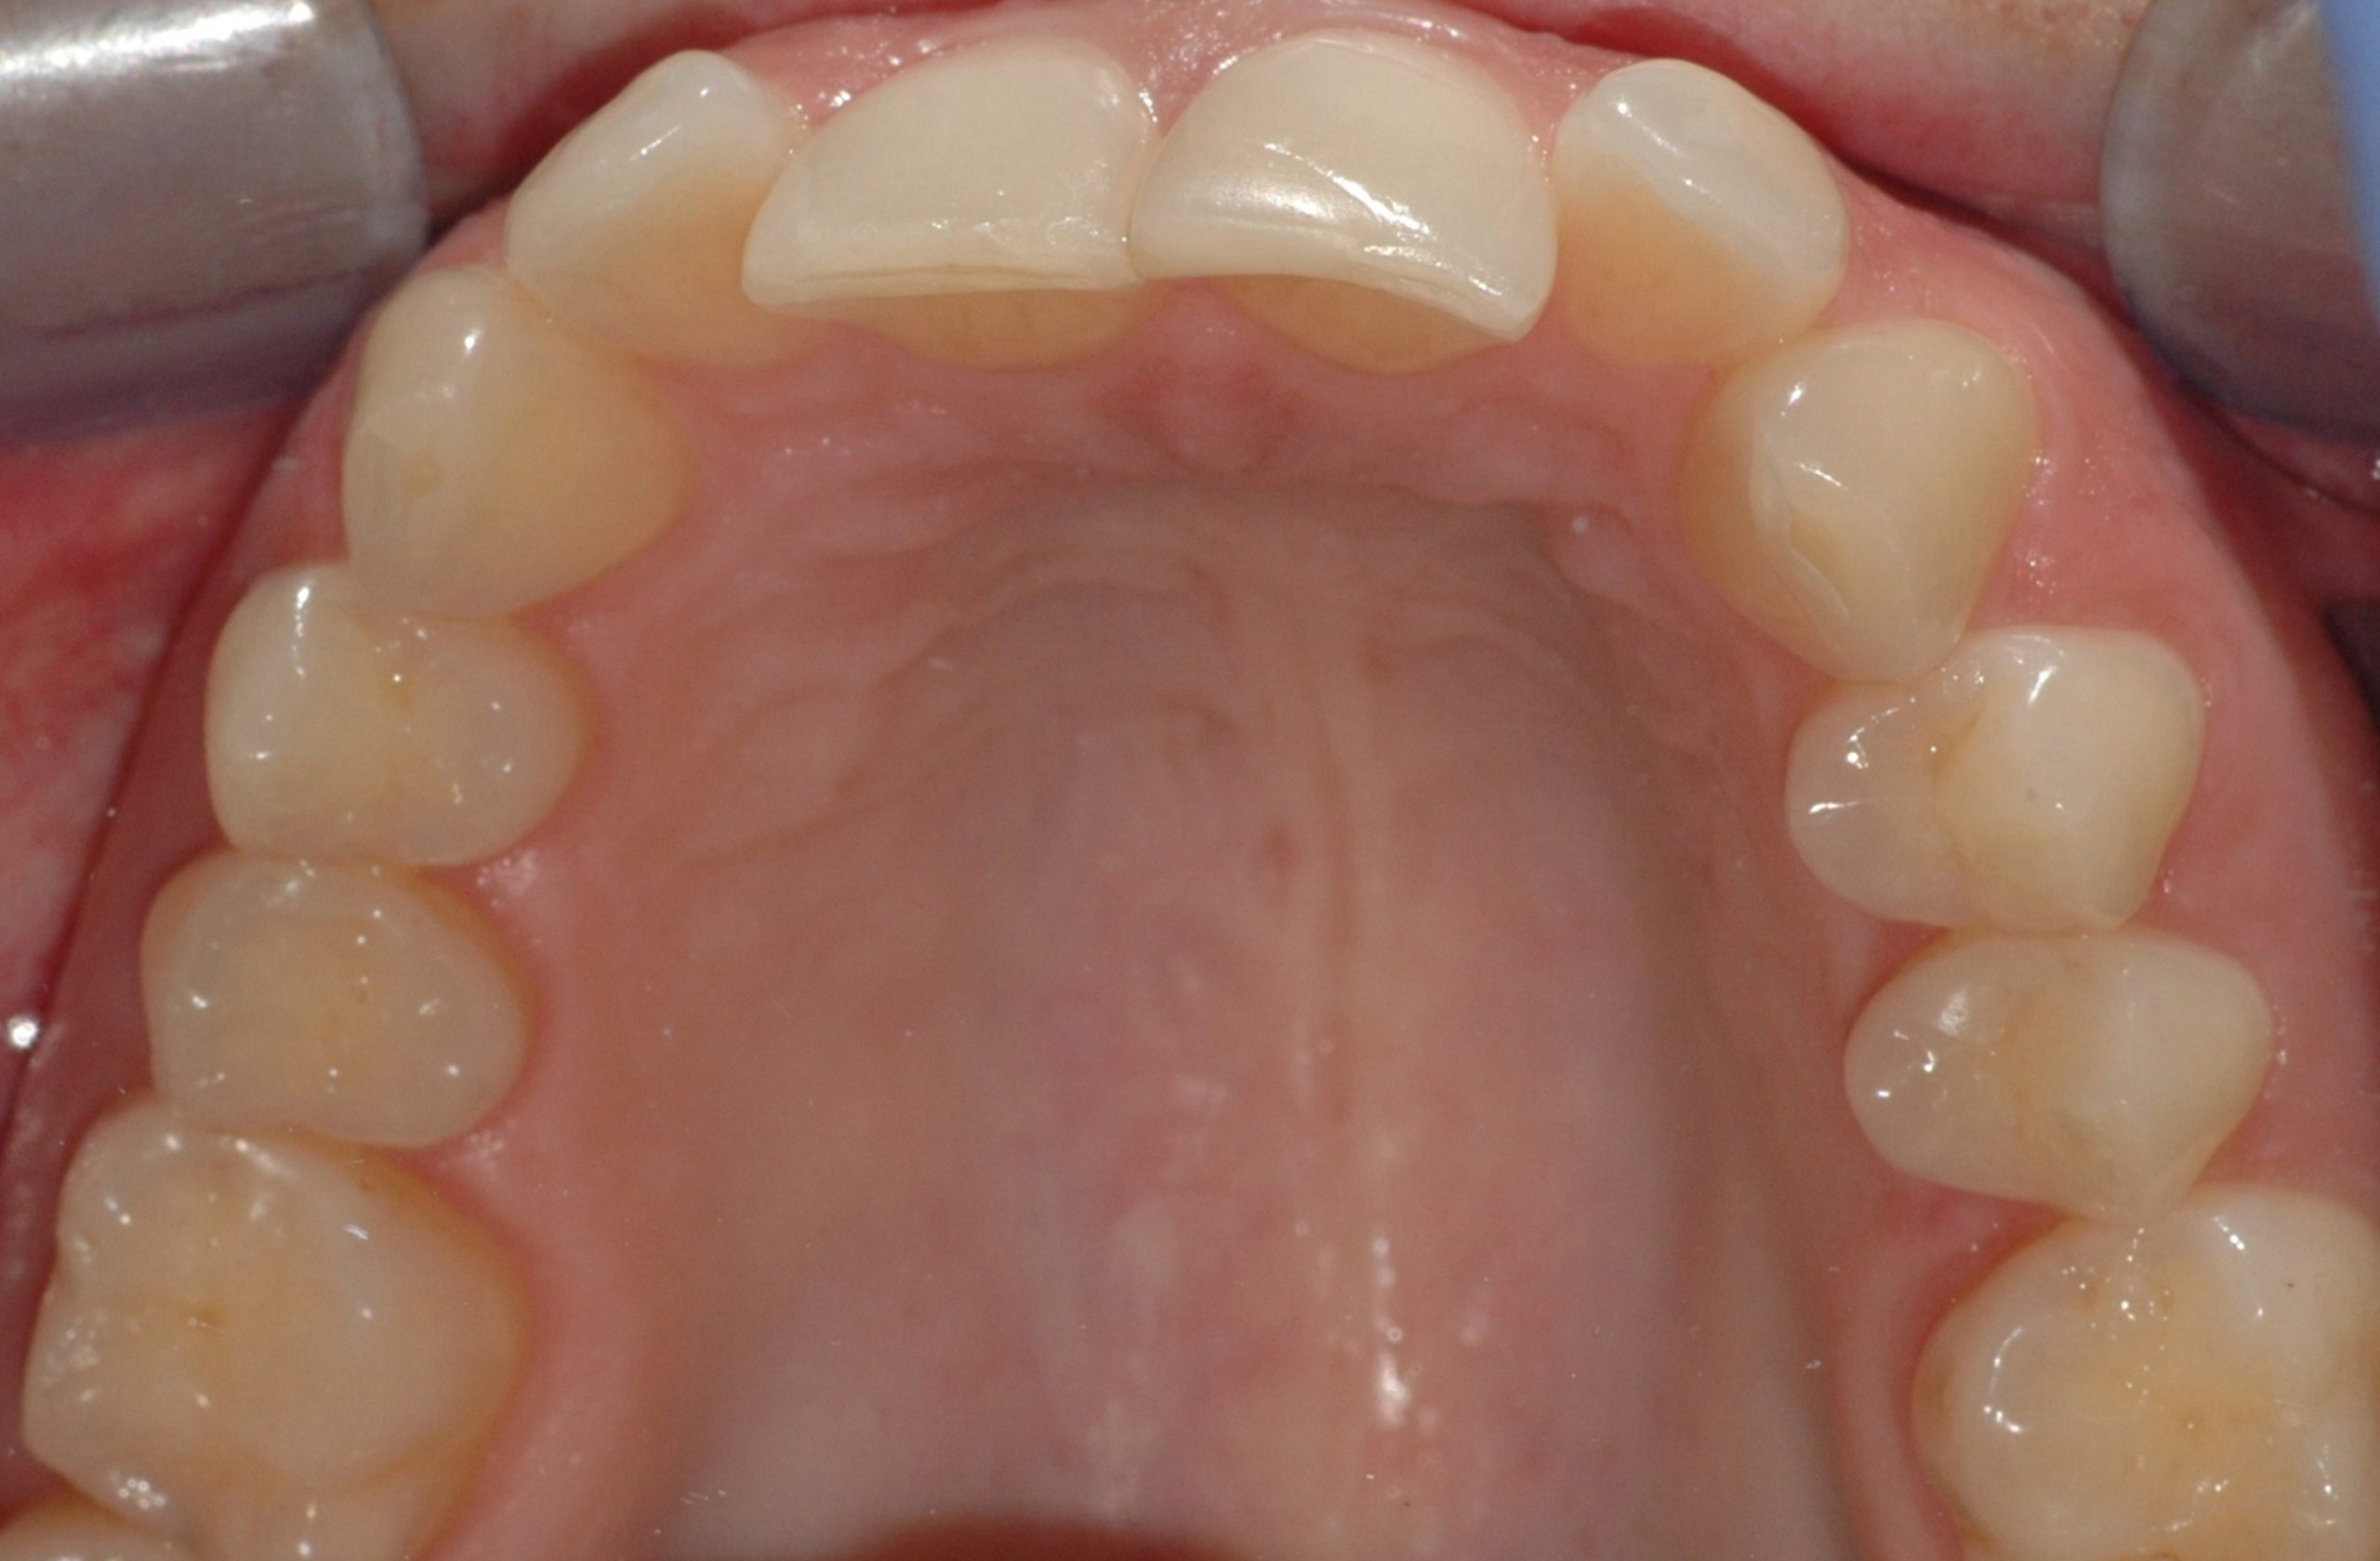

Caso clinico

La paziente presenta malposizione degli incisivi antero-superiori, in particolare un forte sventagliamento degli incisivi laterali. In seguito a trattamento con allineatori trasparenti, durato 9 mesi, si è ottenuto un allineamento pienamente soddisfacente.

PRIMA

DOPO